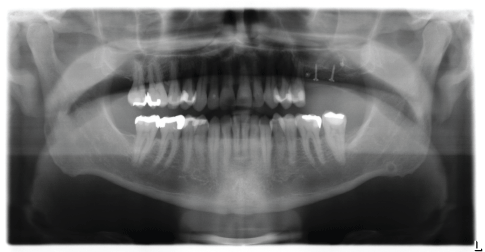

2015年,在经过全面评估和筛选、微生物鉴定(图2,Hauss Laboratory, Kiel)和放射学评估(图3)后,患者最初被处方125 mg阿莫西林500/克拉维酸(1-1-1超过10天)作为全封闭刮除术的佐剂。

当患者再次评估时,在14、15、24和25牙周围观察到探针深度增加至12 mm。放射学检查显示有明显的垂直骨缺损,并伴有探测出血(BOP),因此计划在14和15颗牙齿周围进行再生牙周手术治疗(图4和5)。